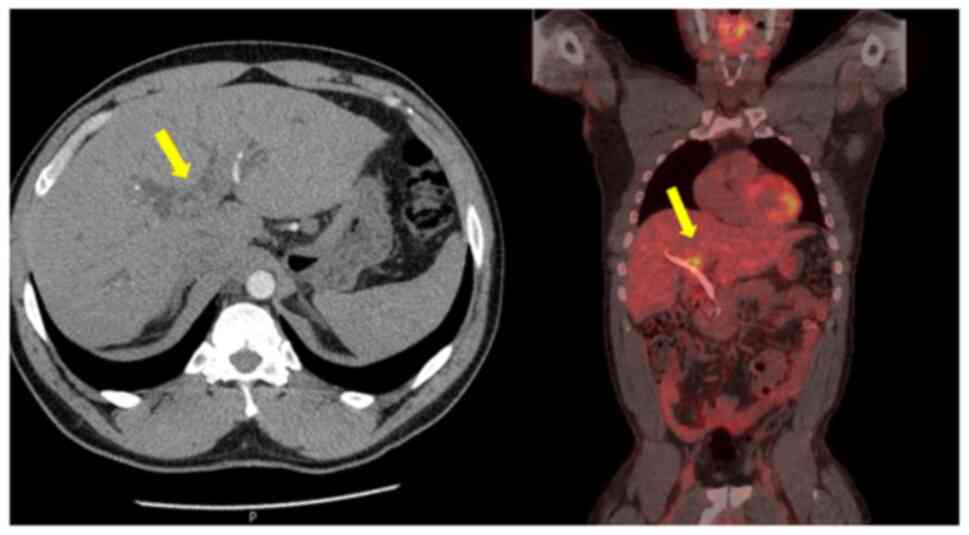

Histological analysis revealed a moderately differentiated perihilar cholangiocarcinoma measuring 21 mm, arising in the setting of biliary intraductal papillary neoplasm of the extrahepatic ducts (30 mm) on a background of severe PSC. Proximal, distal, and circumferential margins were negative for malignancy. Perineural (PN) and lymphovascular (LV) invasion were both present. Final pathological staging was pT2aN0 (0/14) PN1LV1R0 (Fig. 4). Fig. 4 depicts routine haematoxylin and eosin (H&E) staining performed by the Department of Histopathology at King s College Hospital. Sections were paraffin-embedded and cut at a standard diagnostic thickness of 3-4 µm. Fixation was performed in 10% neutral-buffered formalin at room temperature for a minimum of 24 h. A standard H&E stain was used, procured from established hospital suppliers under ISO-accredited protocols. Staining was carried out using automated staining systems under standard diagnostic laboratory conditions. Microscopic evaluation was performed using a Leica DM1000 microscope. These procedures are in accordance with institutional diagnostic protocols.

Haematoxylin and eosin staining

demonstrating a moderately differentiated tubular adenocarcinoma,

consistent with perihilar cholangiocarcinoma (original

magnification, x400; indicative scale bar, ~50 µm).

Figure 4

Haematoxylin and eosin staining demonstrating a moderately differentiated tubular adenocarcinoma, consistent with perihilar cholangiocarcinoma (original magnification, x400; indicative scale bar, ~50 µm).